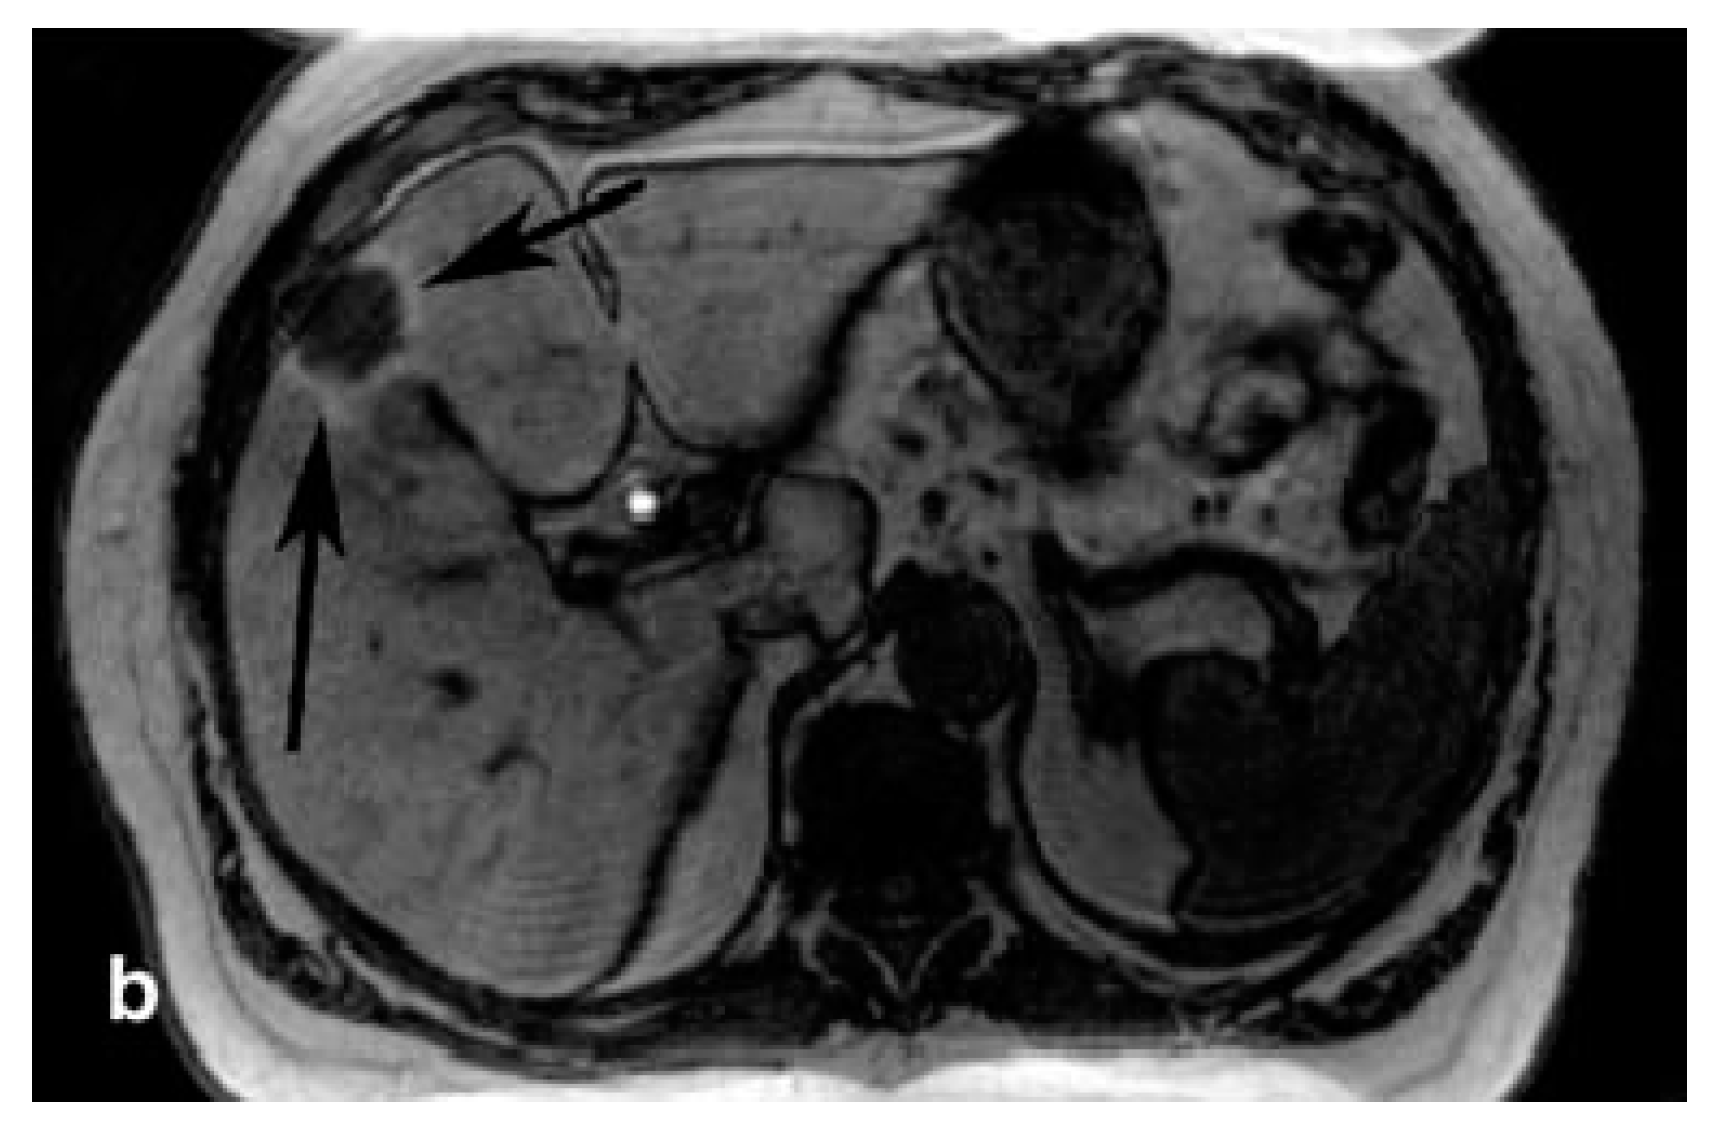

- Watcharin, W.; Zeuzem, S.; Piiper, A.; Schmithals, C.; Pleli, T.; Koberle, V.; Korkusuz, H.; Huebner, F.; Vogl, T.J.; Korf, H.W.; et al. Biodegradable human serum albumin nanoparticles as contrast agents for the detection of hepatocellular carcinoma by magnetic resonance imaging. Eur. J. Pharm. Biopharm. 2014, 87, 132–141. [Google Scholar] [CrossRef] [PubMed]

- Watcharin, W.; Schmithals, C.; Pleli, T.; Koeberle, V.; Korkusuz, H.; Huebner, F.; Waidmann, O.; Zeuzem, S.; Korf, H.-W.; Terfort, A.; et al. Detection of hepatocellular carcinoma in transgenic mice by Gd-DTPA- and rhodamine 123-conjugated human serum albumin nanoparticles in T1 magnetic resonance imaging. J. Control. Release 2015, 199, 63–71. [Google Scholar] [CrossRef] [PubMed]